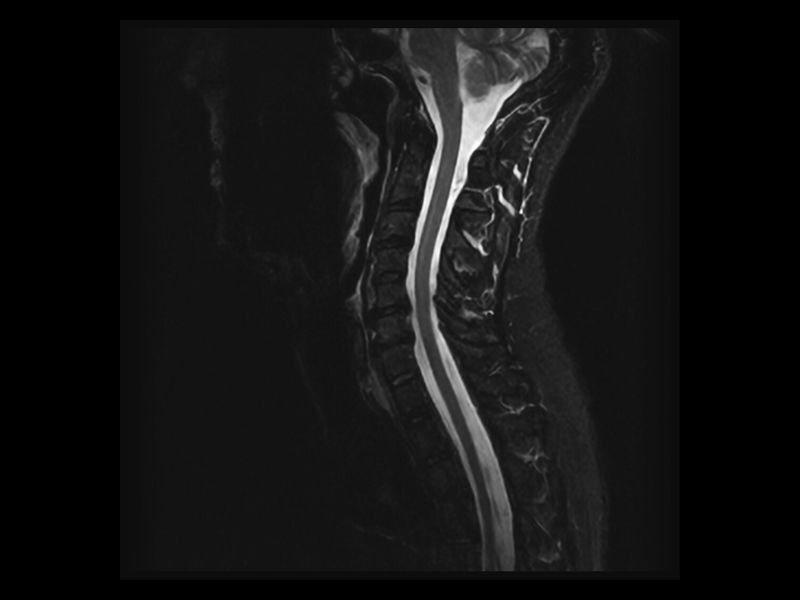

Esaote introduces Artificial Intelligence into its MRI systems as a fully integrated and customized solution. The new technological platform, e‑SPADES, consisting of advanced HW and sophisticated SW algorithms such as HyperClarity delivers unparalleled image quality.

Step into a new era for Esaote systems with HyperClarity, powered by SwiftMR™, a trademark of AIRS Medical Inc. This advanced integrated feature significantly enhances image quality by improving resolution, reducing noise, and providing physicians with a powerful tool for more consistent clinical outcomes.

Clinical Images